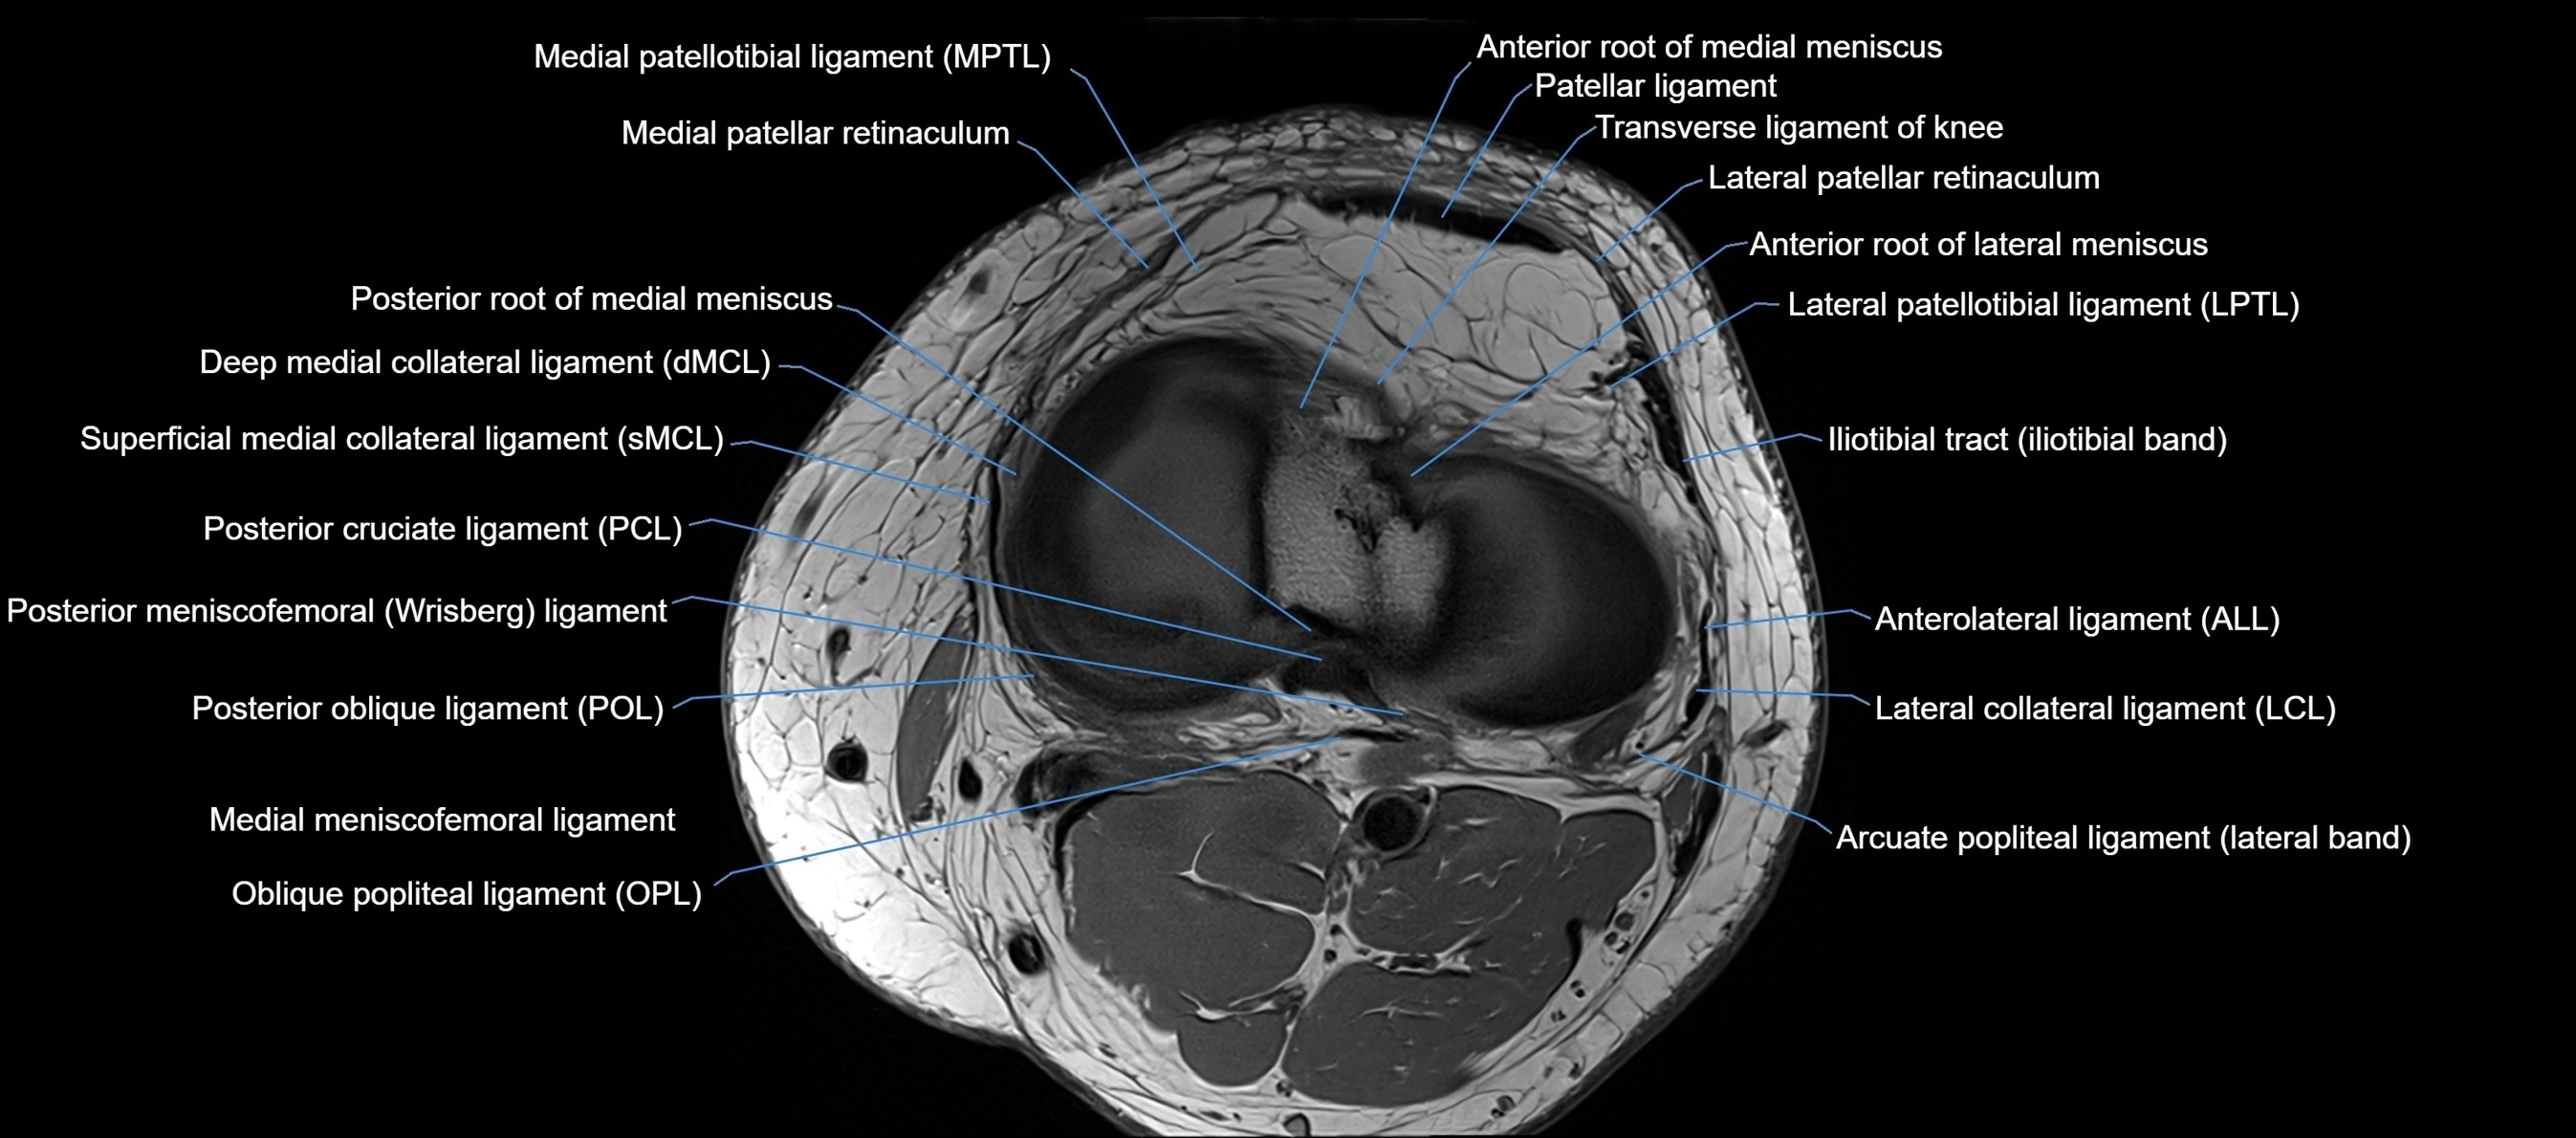

MRI images

image